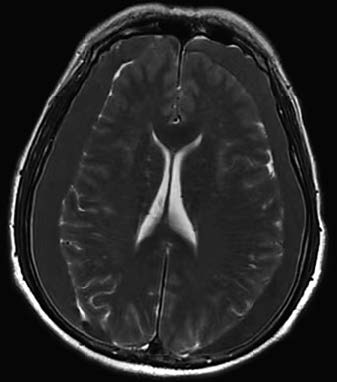

Chronic subdural hematomas are prone to misdiagnosis or missed diagnosis. Elderly individuals presenting with symptoms of chronic intracranial pressure increase, intellectual and psychological abnormalities, or neurological dysfunction, especially with a recent history of minor head trauma, should be evaluated for the possibility of chronic subdural hematoma. Timely CT or MRI can confirm the diagnosis. CT imaging reveals crescent-shaped or semilunar hypodense or isodense lesions over the brain surface. MRI shows crescent-shaped or semilunar lesions with low T1 and high T2 signal intensities.

Figure 2 Chronic subdural hematoma (MRI, bilateral frontoparietal lobes)